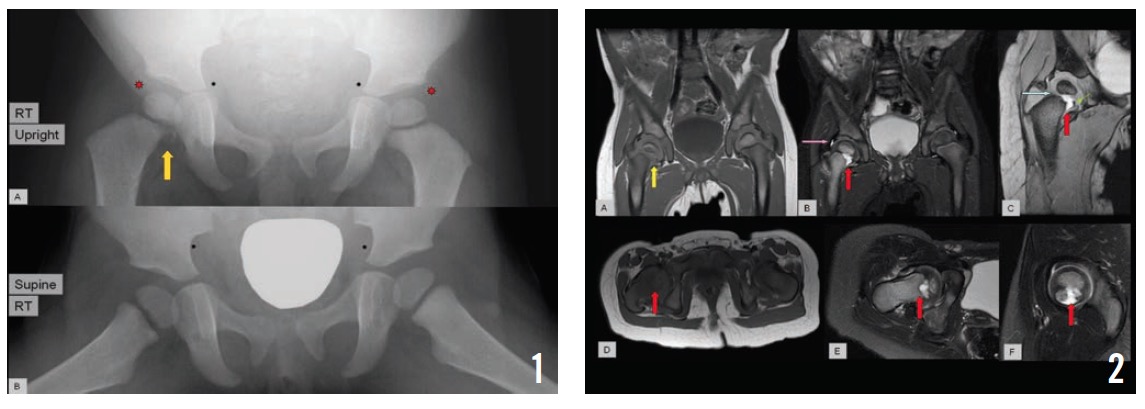

Repeat radiographs of the right knee joint, tibia, and fibula in the orthopedic clinic were unremarkable, but a pelvic radiograph showed a small lytic area with irregularity in the right proximal medial femur (Figure 1).